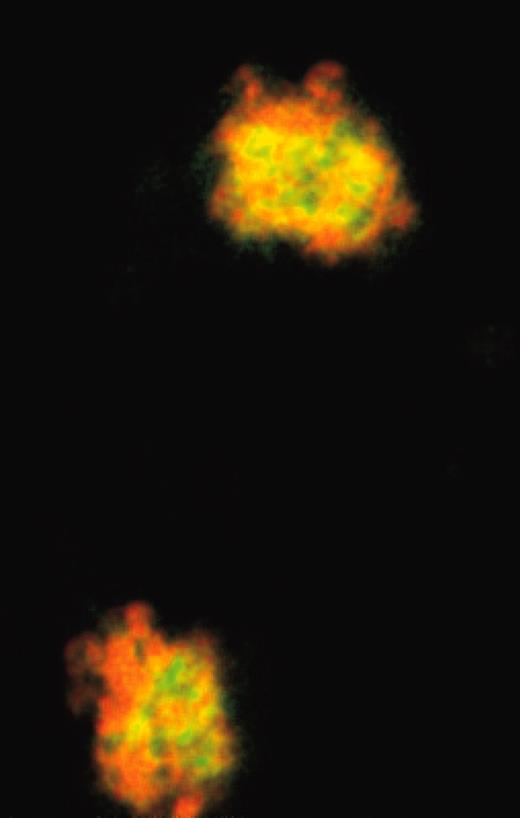

Interaction of IAC-1 to platelets deposited on collagen under flow. See the complete figure in the article beginning on page 390.

The crystal structure of a 21-residue collagen peptide bound to the α2 I-domain revealed that 3 loops on the upper surface of the I-domain coordinate a metal ion and bind to collagen.5 However, IAC-1 binds to an epitope on the opposite side of the I-domain. This means that platelet stimulation induces a global change in the I-domain conformation. More important from the standpoint of future experimentation, it means that collagen and IAC-1 can bind to the I-domain simultaneously, enabling the antibody to detect activated α2βl when platelets adhere to a collagen-coated surface.FIG1